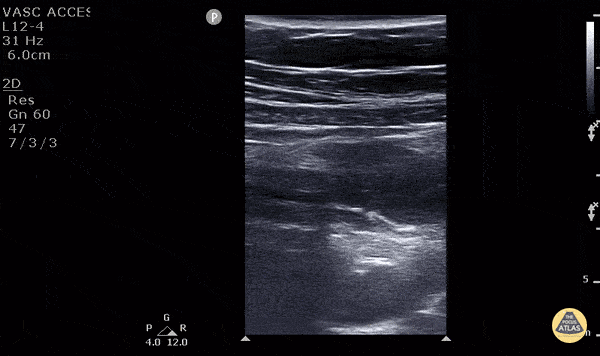

11 y/o M presented with 1 day of periumbilical pain that migrated to the right lower quadrant with nausea, vomiting and anorexia. Ultrasound with high frequency linear probe demonstrates an enlarged appendix with an external diameter of 1.32 cm with trace free fluid posteriorly, as well as a fecalith at the proximal end of the appendix. Surgery was consulted who requested a formal US which was non-diagnostic. Surgery took the patient anyway, and MRI confirmed our findings (including the large diameter). Diagnostic criteria for appendicitis: a non-compressible, aperistaltic, blind ended structure >6mm diameter. Visualizing free fluid, tenderness in that area, and visualizing a fecalith can also add to the diagnosis. See the evidence atlas for more info about POCUS diagnosing appendicitis but when visualizing a diagnostic appendicitis, it carries a positive likelihood ratio of 9.24. PMID: 28214369 Jackie Chiou MS4, Dr. Matthew Riscinti and Dr. Tian Liang - Kings County Emergency Medicine